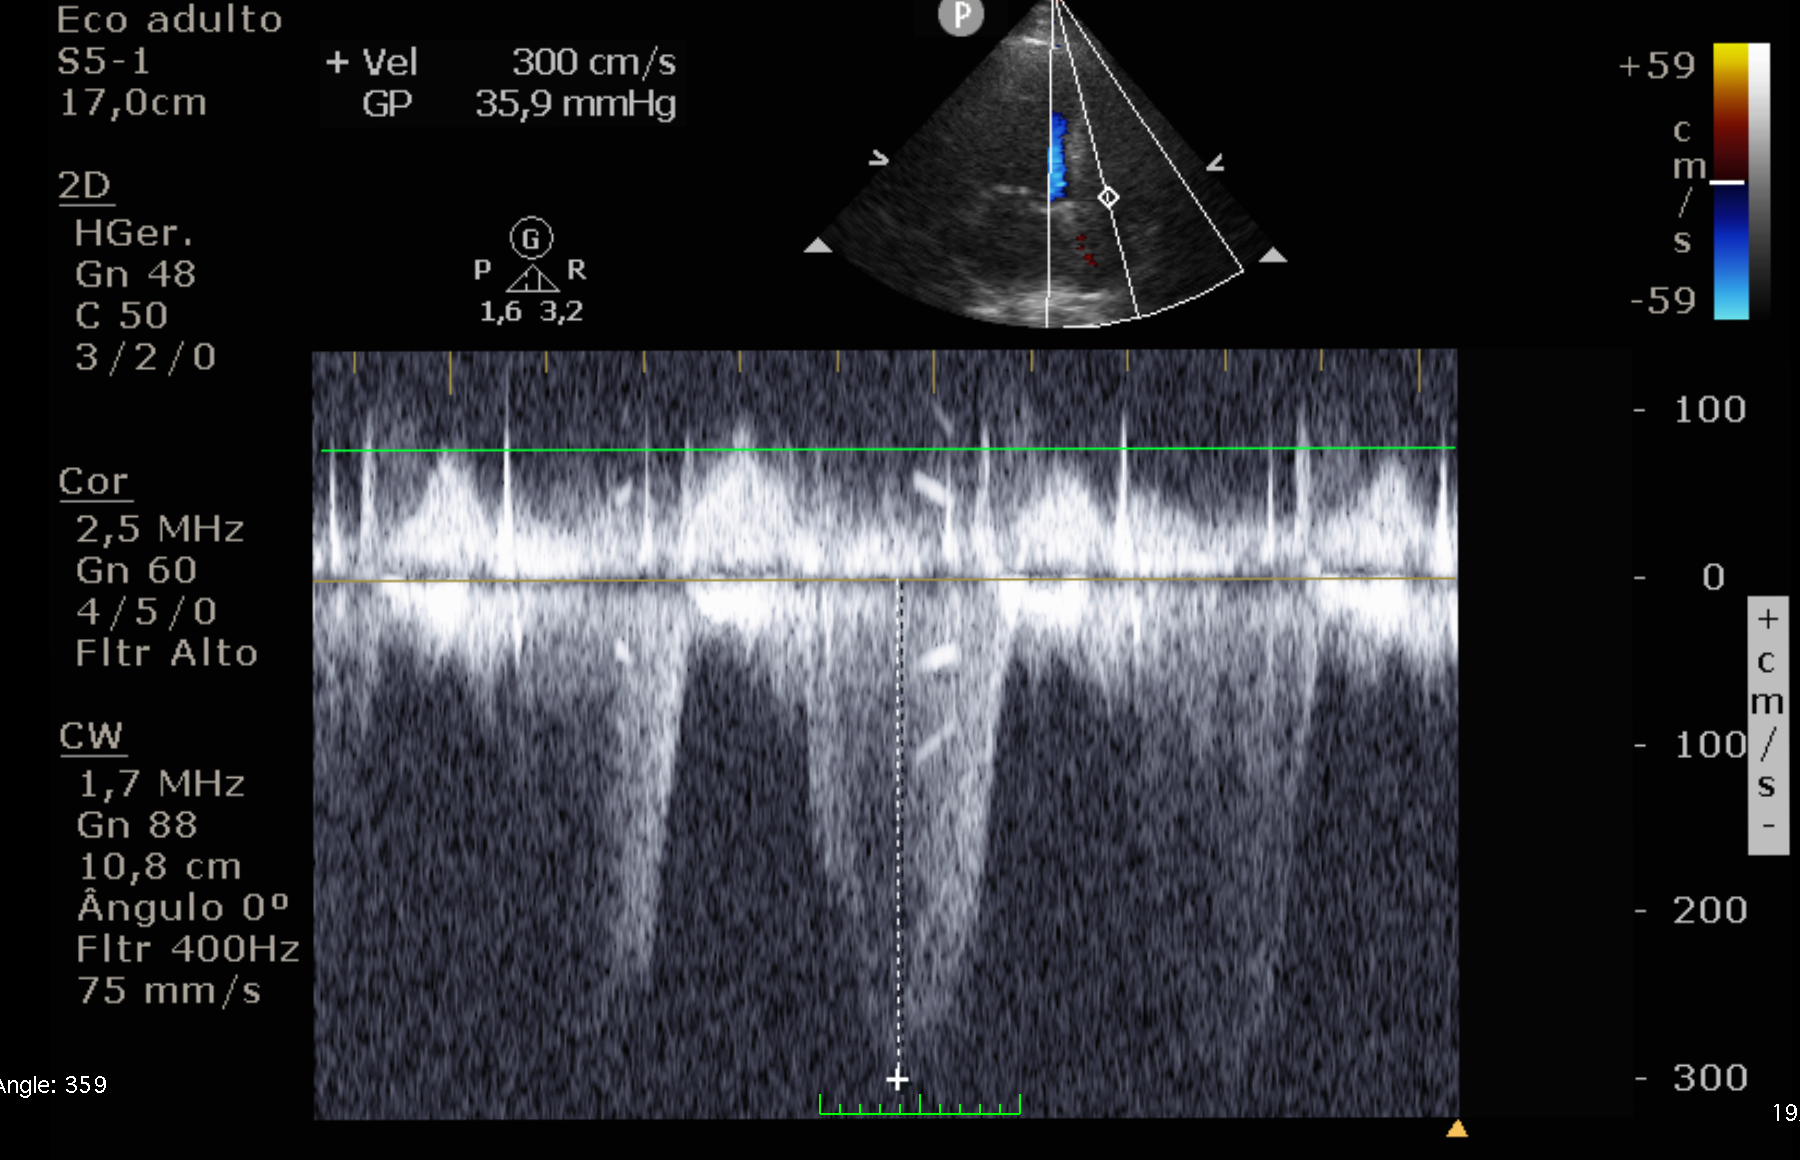

Velocidade Regurgitação Tricúspide (VRT) ≤ 2,8 m/s > 2,8 m/s (Probabilidade Intermediária)

> 3,4 m/s (Alta Probabilidade)

Pressão Média da Artéria Pulmonar (PMAP)* < 20 mmHg > 20 mmHg

*Nota importante (ASE 2025): A definição de Hipertensão Pulmonar mudou o corte de PMAP de ≥25 para >20 mmHg.